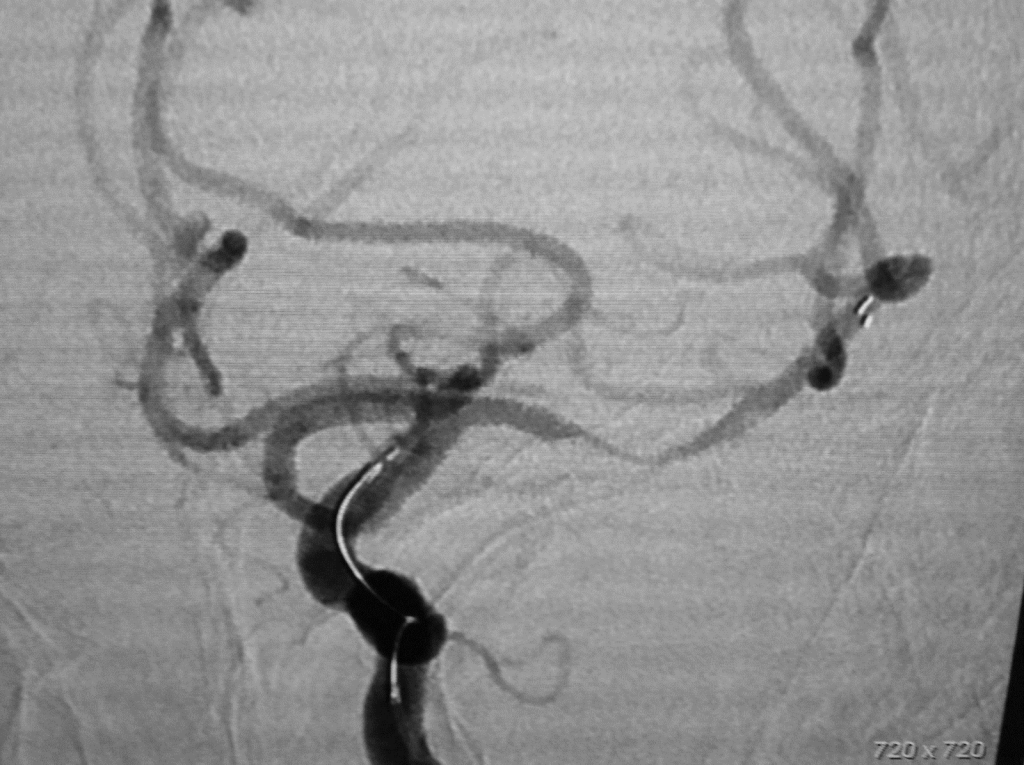

Stent retriever inserted into Middle Cerebral Artery (red arrows point to the markers bands of the stent retriever)